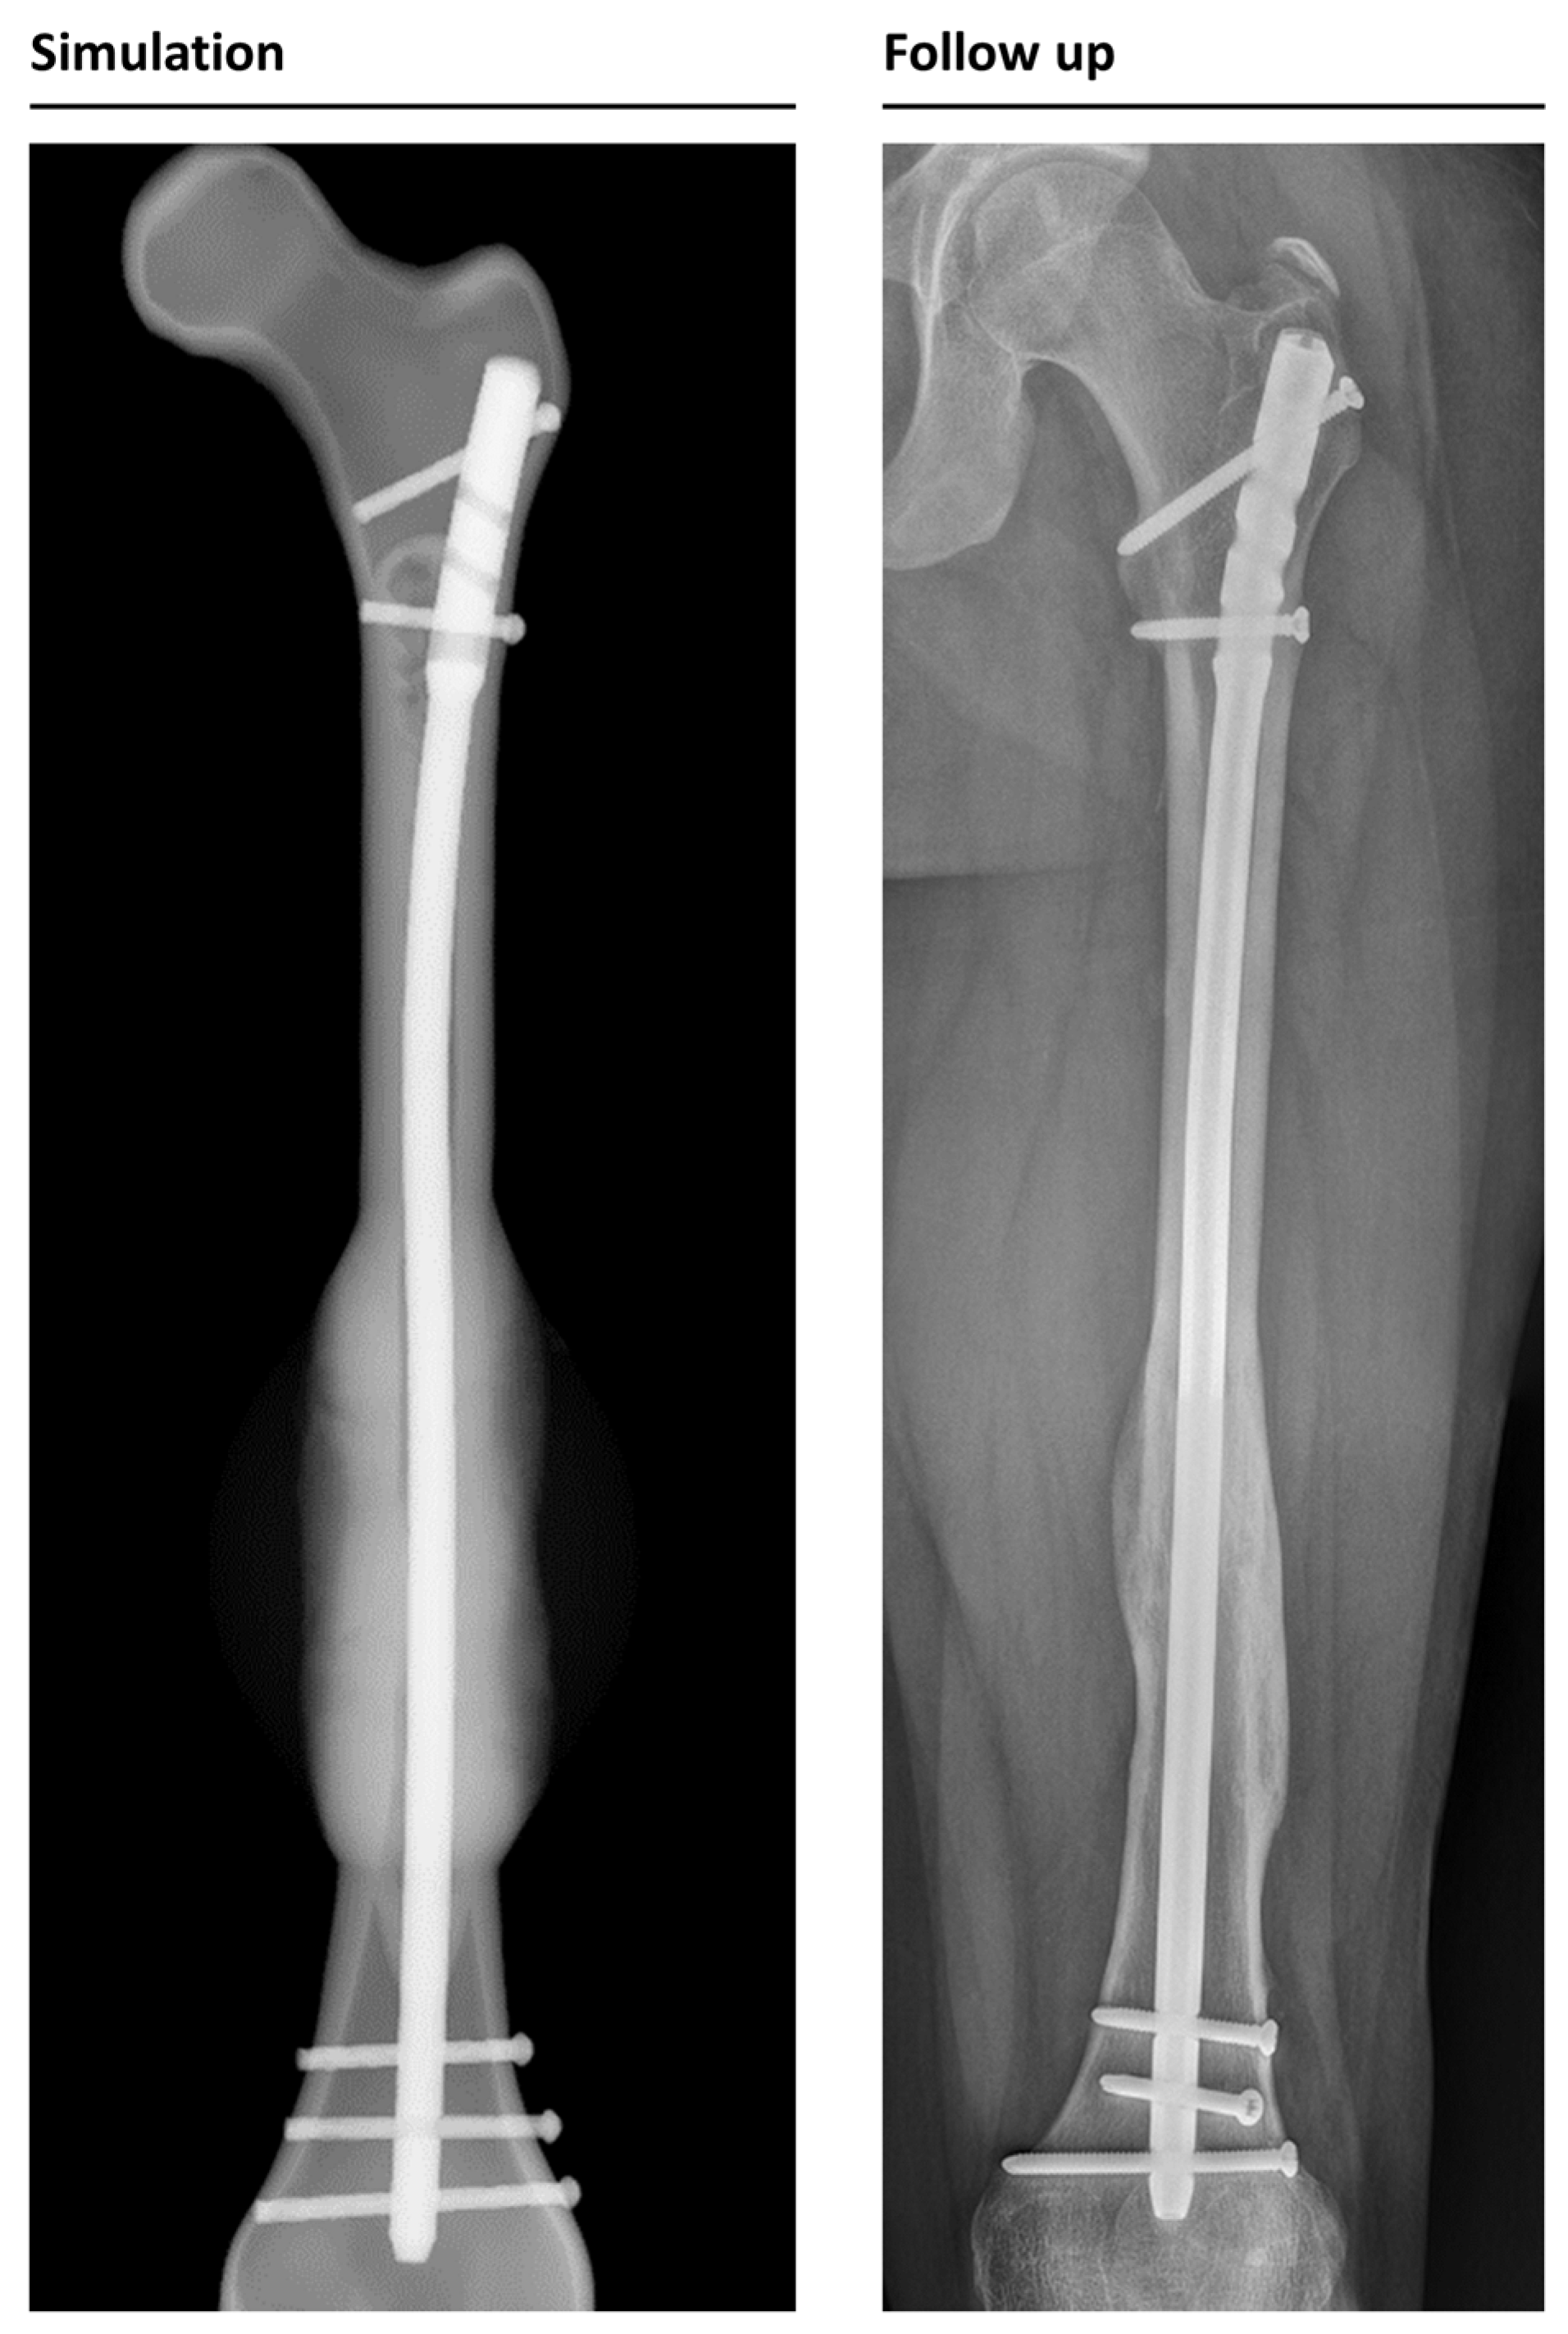

Figure 6. Callus formation in the simulation and follow-up X-ray data in anterior-posterior view. Follow-up was taken 31 weeks after surgery; simulation shows the same timeframe.